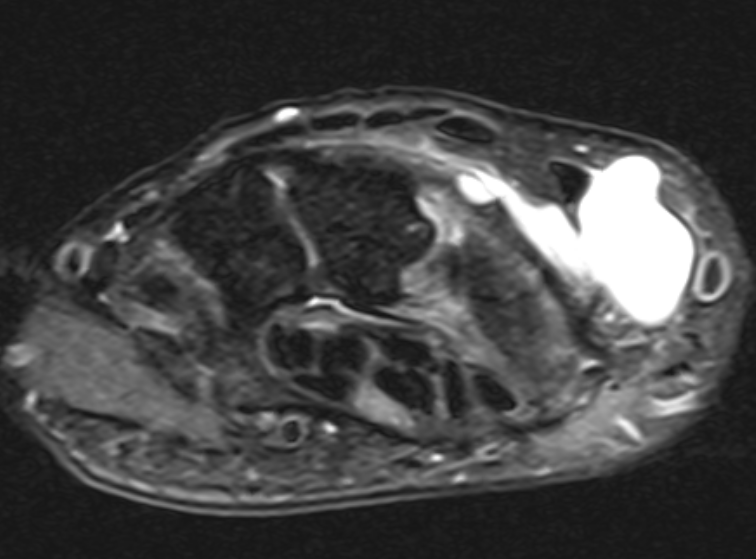

Volar ganglion